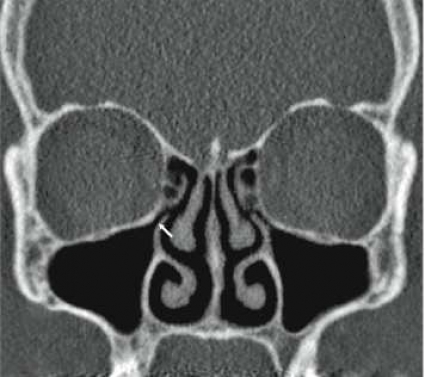

Initiala fantomstudier och pilotundersökningar visade, som förväntat, att bildkvaliteten med lågdosprotokollet blev sämre än med standardprotokollet, men den bedömdes ändå som fullt tillräcklig för den diagnostiska uppgift som avses med en konventionell röntgenundersökning av bihålorna (Figur1). Det diagnostiska värdet av lågdos-DT bedömdes av både radiologer och örondoktorer som klart överlägset värdet av en vanlig röntgenundersökning, och dosberäkningar visade också att stråldosen var lägre för lågdos-DT än för konventionell röntgenundersökning.

Resultaten visar klart att lågdos-DT ger bra visualisering av samtliga näsans bihålor, och man kunde med lätthet både påvisa och utesluta engagemang av såväl frontalsinus som sfenoidalsinus och inte minst av etmoidalsinus, ett område där den konventionella teknikens tillkortakommanden är väl kända. Lågdos-DT visade sig också möjliggöra en diagnostisk bedömning av anatomiska nyckelstrukturer såsom infundibulum och frontonasala recessen.

Användandet av lågdos-DT innebär sålunda inte bara en säkrare diagnostik av bihåleförändringar än med vanlig röntgenundersökning, utan man får också viktig tilläggsinformation, som inte kan erhållas med vanlig röntgenundersökning. Även möjligheten att visualisera små, men kliniskt relevanta anatomiska avvikelser (tex concha bullosa, Haller-celler och dysplasier), postoperativa förändringar, benförändringar vid kronisk sinuit och odontogena orsaker till sinuit, gör lågdos-DT klart överlägsen konventionell röntgenundersökning vid sinuit (Figur2).